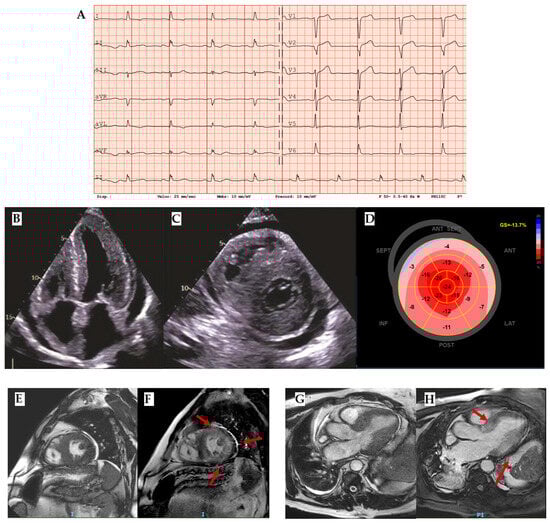

Amyloidosis involves the heart as a whole. Indeed, on an echocardiogram, it is characterized by an interventricular septum diameter greater than 12 cm, a granular sparkling appearance, normal to small LV cavity size (restrictive physiology), biatrial enlargement and dysfunction with left atrial and left appendage stasis and thrombi, interatrial septal and right ventricular thickening, pericardial effusion, diastolic dysfunction with restrictive transmitral Doppler filling pattern (steep deceleration time, low tissue Doppler velocity at the mitral annulus and an elevated E/e’ ratio), and aortic stenosis [27] (Figure 5B–D).

Even in the earlier phases of the disease there is impairment of longitudinal systolic function, while radial thickening and circumferential shortening are still preserved. This feature can be analyzed by speckle tracking echocardiography, with the evidence of abnormal longitudinal strain in the basal and mid segments with relative preservation in the apical segments, as shown in the Global Longitudinal Strain bullseye map with the cherry-on-the-top sign (Figure 5D) [23,28].

Tissue characterization provided by CMR is fundamental in the diagnostic work-up of amyloidosis, helping in differential diagnosis. The main features are high native T1 and LGE with a subendocardial or a transmural pattern (Figure 5E–H) [11]. Radionuclide imaging, especially bone scintigraphy with the use of 99mTc-labeled diphosphonate, plays a central role in the noninvasive diagnosis of ATTR cardiac amyloidosis, with high sensitivity and specificity, especially for Perugini’s score Grade 2–3 (heart capitation of the tracer visually equal or super than that in bone). Indeed, according to the consensus algorithm proposed by Gillmore et al. for the differential diagnosis between AL and ATTR, serum/urine immunofixation, serum light chain assay, and bone scintigraphy are the mandatory steps for noninvasive diagnosis [29]. On the other hand, the role of nuclear imaging, particularly PET, in the diagnosis of cardiac amyloidosis and its potential for distinguishing between AL and ATTR is under investigation [30].

Figure 5. Amyloidosis. (A) ECG with an important mismatch between cardiac hypertrophy and electrical voltage in a patient with ATTR and severe cardiac hypertrophy with 23 mm septum thickness: low voltages are observed in peripheral leads and normal voltages in precocardial leads. (B) Four chamber and (C) short-axis 2 chamber showing not only left ventricle hypertrophy but also other typical findings in amyloidosis such as right ventricle hypertrophy, thick interatrial septum, Coumadin ridge, and cardiac valves. (D) Reduced Global Longitudinal Strain (GLS) with apical sparing and the typical cherry-on-the-top sign. (E) Cine-bSSFP short-axis 2-chamber view, (F) LGE short-axis 2-chamber view (red arrows highlight the LGE segments), (G) Cine-bSSFP 3-chamber view, and (H) LGE 3-chamber view of a patient with severe cardiac ATTR with transmural LGE in all mid segments except the inferior septum and basal antero-septum and infero-lateral walls (red arrows). ATTR: transthyretin amyloidosis.